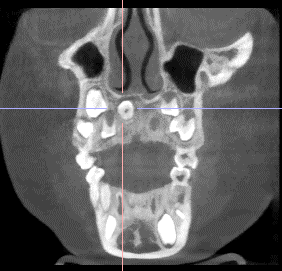

8岁的小林在一次口腔检查中偶然发现上颌藏有一颗额外牙齿。通过检查,医生清晰地看到一颗完全倒置的额外牙隐藏在上颌前牙区,紧邻正常牙根、鼻腔底部和鼻腭神经等重要结构。这颗牙齿位置特殊,传统手术方法存在视野受限和损伤风险。

医疗团队为小林量身定制了“前鼻棘翻瓣”微创手术方案。以前鼻棘为精准定位标志,结合CBCT影像导航,通过微小切口和超声骨刀精细操作,就能安全完整地取出埋伏牙,最大限度地保护了周围重要结构。术后小林恢复迅速,面部肿胀轻微,正常牙齿发育未受影响,定期复查显示恢复效果理想。